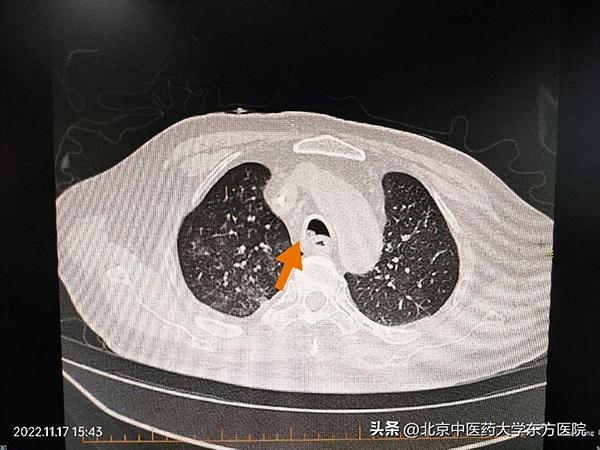

CT箭头指向支气管异物嵌顿处